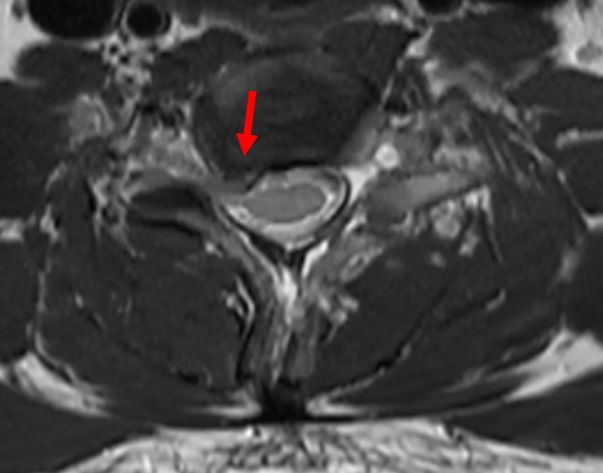

磁共振检查发现颈椎间盘脱出

诊断神经根型颈椎病

红色箭头:颈椎间盘突出,

颈肩、上肢疼痛的“罪魁祸首”